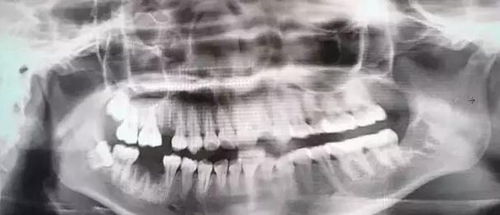

下面這兩張圖,據(jù)說拔牙費時1.5小時,收費14000元。

6.jpg

7.jpg